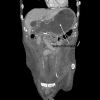

Cast syndrome, commonly known as superior mesenteric artery (SMA) syndrome is a rare cause of small bowel obstruction caused by compression of third part of duodenum from narrowing of the angle between superior mesenteric artery and abdominal aorta resulting in symptoms of duodenal outflow obstruction. A 46-year-old male presented with acute worsening of chronic abdominal pain, nausea and vomiting aggravated with eating. Computed tomography of abdomen and pelvis revealed the dilatation of gastric and proximal duodenum due to compression of third part of duodenum between superior mesenteric artery and aorta. Conservative management with total parental nutrition failed and patient underwent gastrojejunostomy with relief of his symptoms. Cast syndrome is a rare condition but should be kept in mind in patients with abdominal pain, vomiting, early satiety and weight loss. CT abdomen usually reveals the diagnosis but upper GI endoscopy helps to rule out other causes of duodenal obstruction and gastric dilatation.